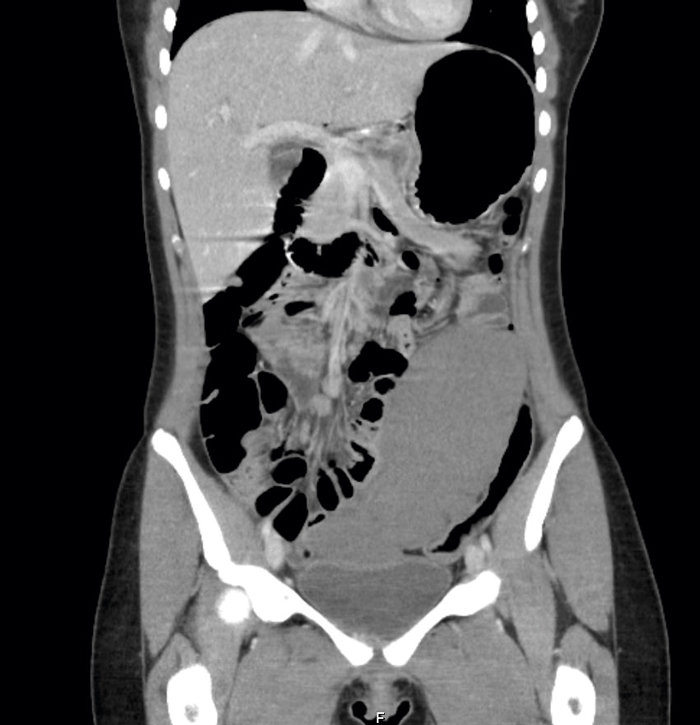

Patienten vårdades på uppvakningsavdelningen och togs sedan direkt till röntgen för att genomgå datortomografi (DT) av buken för att visualisera cirkulationen till mjälten och för att utesluta en eventuell mjältinfarkt (Figur 1). DT-buk visade sammanfattningsvis en bild förenlig med vandrande mjälte, torsion av arteria och vena lienalis samt kraftigt nedsatt parenkymperfusion med hotande nekros.

Figur 1. Stor mjälte belägen i vänster fossa. Bild tagen efter diagnostisk laparoskopi.